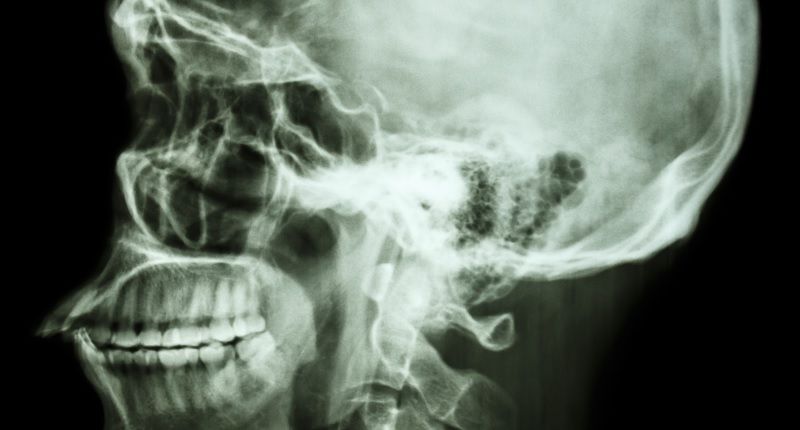

Medical images and health data belonging to millions of Americans, including X-rays, MRIs and CT scans, are sitting unprotected on the internet and available to anyone with basic computer expertise.

The records cover more than 5 million patients in the U.S. and millions more around the world. In some cases, a snoop could use free software programs — or just a typical web browser — to view the images and private data, an investigation by ProPublica and the German broadcaster Bayerischer Rundfunk found.

All told, medical data from more than 16 million scans worldwide was available online, including names, birthdates and, in some cases, Social Security numbers.

The privacy problem traces back to the medical profession’s shift from analog to digital technology. Long gone are the days when film X-rays were displayed on fluorescent light boards. Today, imaging studies can be instantly uploaded to servers and viewed over the internet by doctors in their offices.